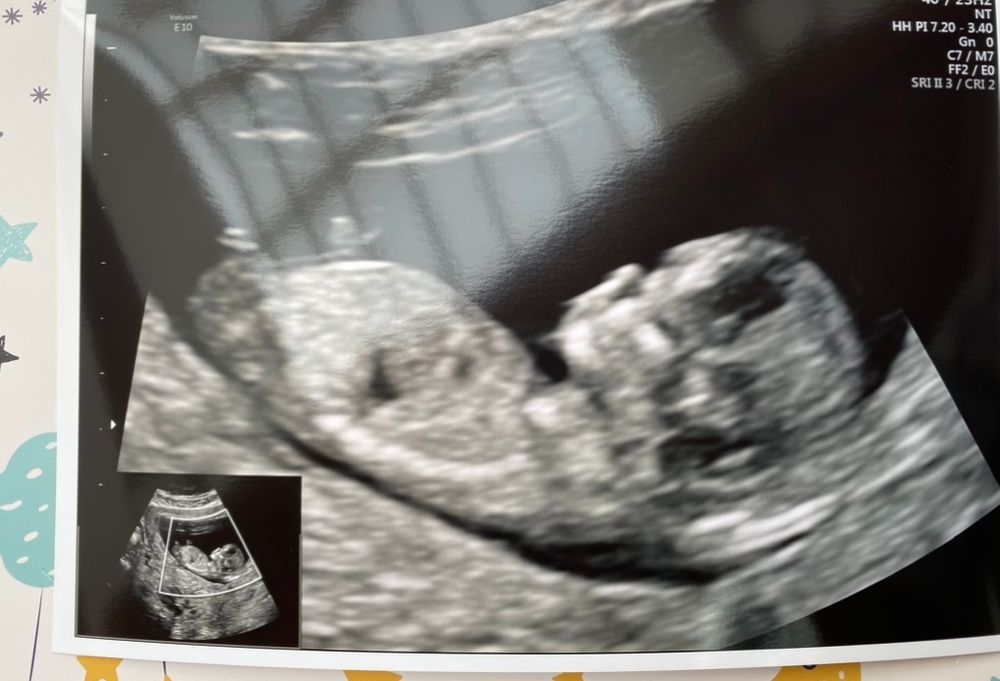

12+6. Первый скрининг позади )

УЗИ в 8 недель после госпитализации. 28 недель 3 дня